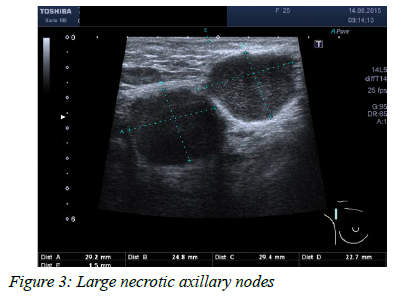

In nodular TB, an ultrasound scan often reveals a well-defined oval hypoechoic mass with posterior acoustic enhancement (Figure 1). The ultrasound picture may resemble a fibroadenoma. These hypoechoic lesions demonstrate no vascularity but rather a fluid collection containing debris. Ultrasound-guided aspiration of purulent fluid distinguishes these lesions from solid breast masses. In the sclerosing form, textural change with no visible fluid may mimic inflammatory carcinoma. The disseminated form of TB is associated with multiple anechoic collections, with and without debris, scattered throughout the breast with or without associated fistulation to the skin (Figure 2). Axillary lymphadenopathy is a common finding in breast TB; lymph nodes can show a spectrum of cortical thickening, solid or necrotic lymph nodes (Figure 3).2025